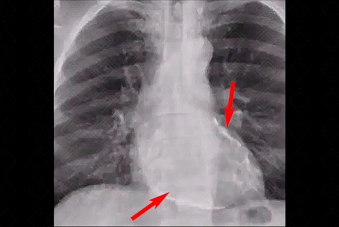

Texto alternativo para a imagem Figura 1. Créditos: Dra. Elazir Mota - Rio de Janeiro/RJ

Descrição da figura 1: Radiografia de tórax evidenciando halo de calcificação ao redor da silhueta cardíaca (setas vermelhas).

Exames de imagem: A calcificação pericárdica pode ser visualizada tanto na radiografia (figura 1) quanto na tomografia computadorizada do tórax (figura 2).

• Radiografia de tórax: Uma imagem radiopaca, curvilínea, envolvendo os bordos cardíacos no estudo em perfil e AP ou PA;